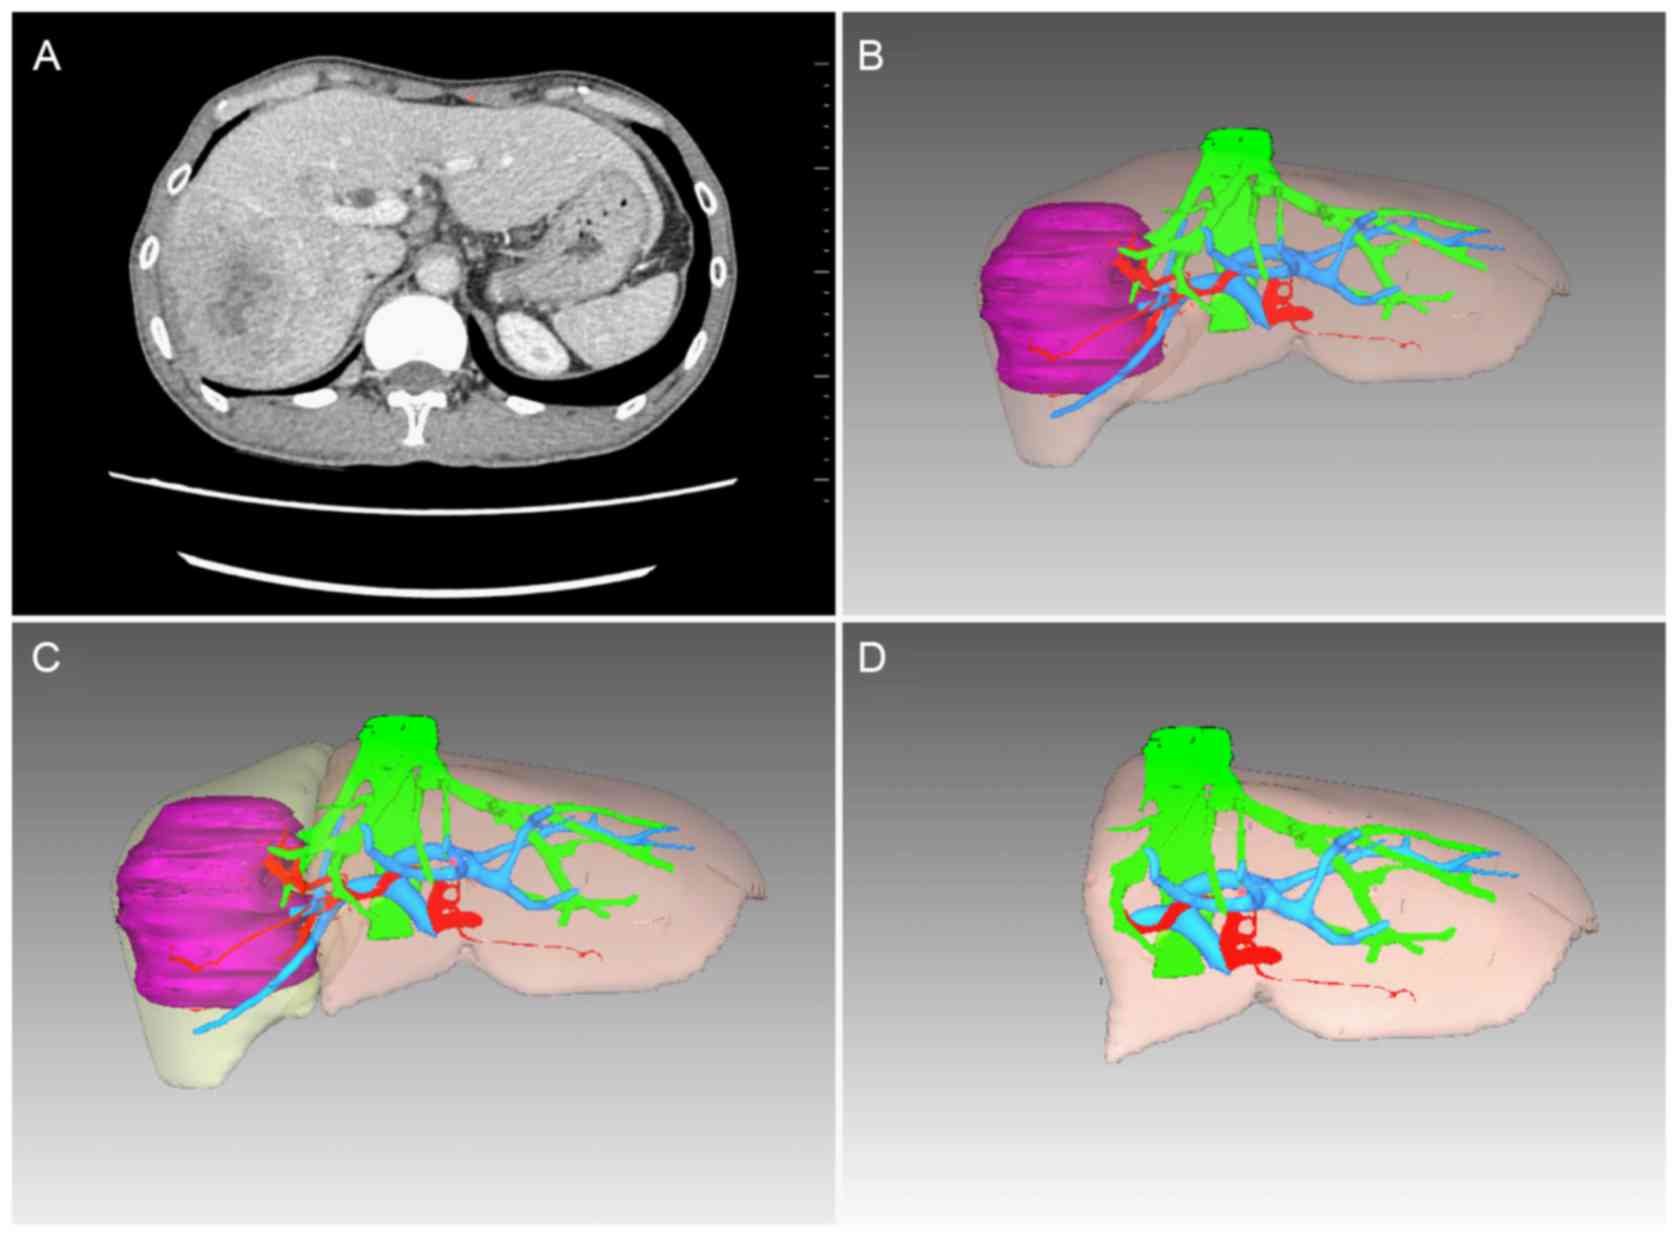

Prior to surgery, all patients underwent a

contrast-enhanced CT angiography scan with a slice thickness of 0.8

mm. Automated volumetry was performed for three-dimensional

reconstruction of the liver using medical image analysis software

(Myrian®; Intrasense S.A.S., Montpellier, France) and

the results were modified by manual contour tracing of the hepatic

contour following automated reconstruction. The gall bladder,

hepatic inferior vena cava and main branches of the intrahepatic

vascular structures were excluded from the reconstructional volume

calculation, but the biliary structures were included. Preoperative

virtual hepatic resection was performed according to the size and

location of the tumors, which were evaluated by two experienced

hepatic surgeons. The liver reconstruction and virtual hepatic

resection are shown in Fig. 1.